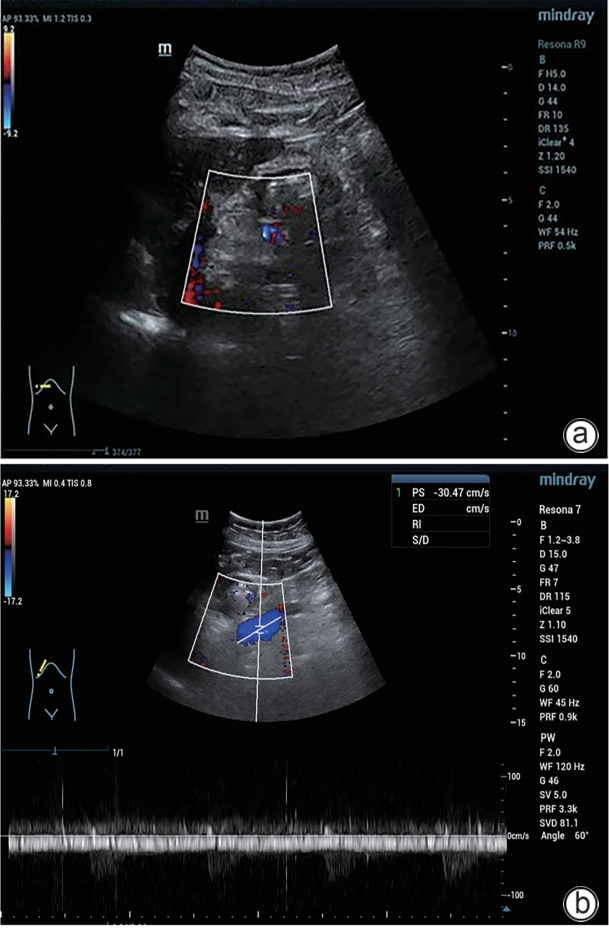

巨大自发性脾肾分流道栓塞联合抗凝治疗门静脉血栓1例报告

门静脉血栓是肝硬化患者常见且严重的并发症,门静脉血流动力学的改变与门静脉血栓的发生密切相关。合并巨大的自发性脾肾分流时门静脉灌注减少、血流速度减慢,极有可能削弱门静脉血栓的抗凝效果。本文将报道1例通过栓塞自发性脾肾分流道联合抗凝治疗策略,实现了门静脉的完全再通,然而,仍需高质量的临床研究进一步验证和支持这一策略的有效性。